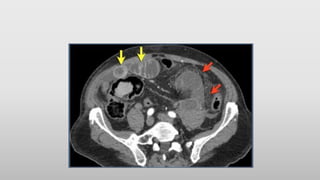

• #15 The CT-image shows nice enhancement of the normal bowel wall (yellow arrows) and no enhancement of the infarcted bowel (red arrows). This would not be visible if positive oral contrast was given.